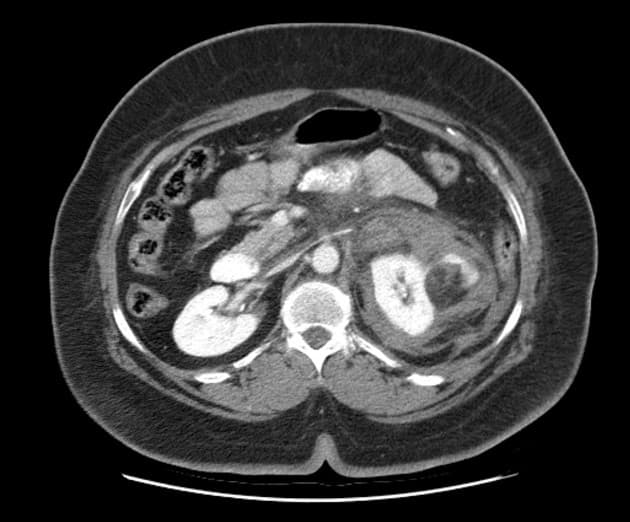

Axial non-contrast

- Ghi nhận khối tổn thương khu trú một phần lồi ra ngoài (exophytic), chứa mỡ, kích thước 25 x 20 mm ở phần giữa của thận phải, trên hình ảnh sau tiêm thuốc cản quang thấy ngấm thuốc (enhancement) không đồng nhất, gợi ý u mỡ cơ mạch thận (angiomyolipoma).

- Các tổn thương này thường có hình ảnh đặc trưng trên chụp cắt lớp vi tính với thành phần mỡ (fat) có tỷ trọng thấp (less than -20 HU).

- Hầu hết tổn thương nằm ở vỏ thận (renal cortex) và chứa mỡ đại thể (macroscopic fat).

U mỡ cơ mạch thận (Renal angiomyolipoma)